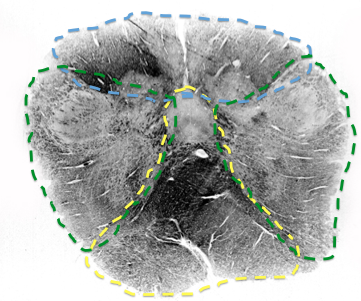

What supplies medial midbrain? for how long? (green)

paramedian branches of the basilar artery supply the midbrain all the way up

What supplies lateral portion of midbrain (blue)? for how long?

PCA

all the way up

als, ml, crus cerebri

what supplies top part of midbrain? for how long?

superior cerebellar, all the way up

supplies notably the inferior and superior colliclus